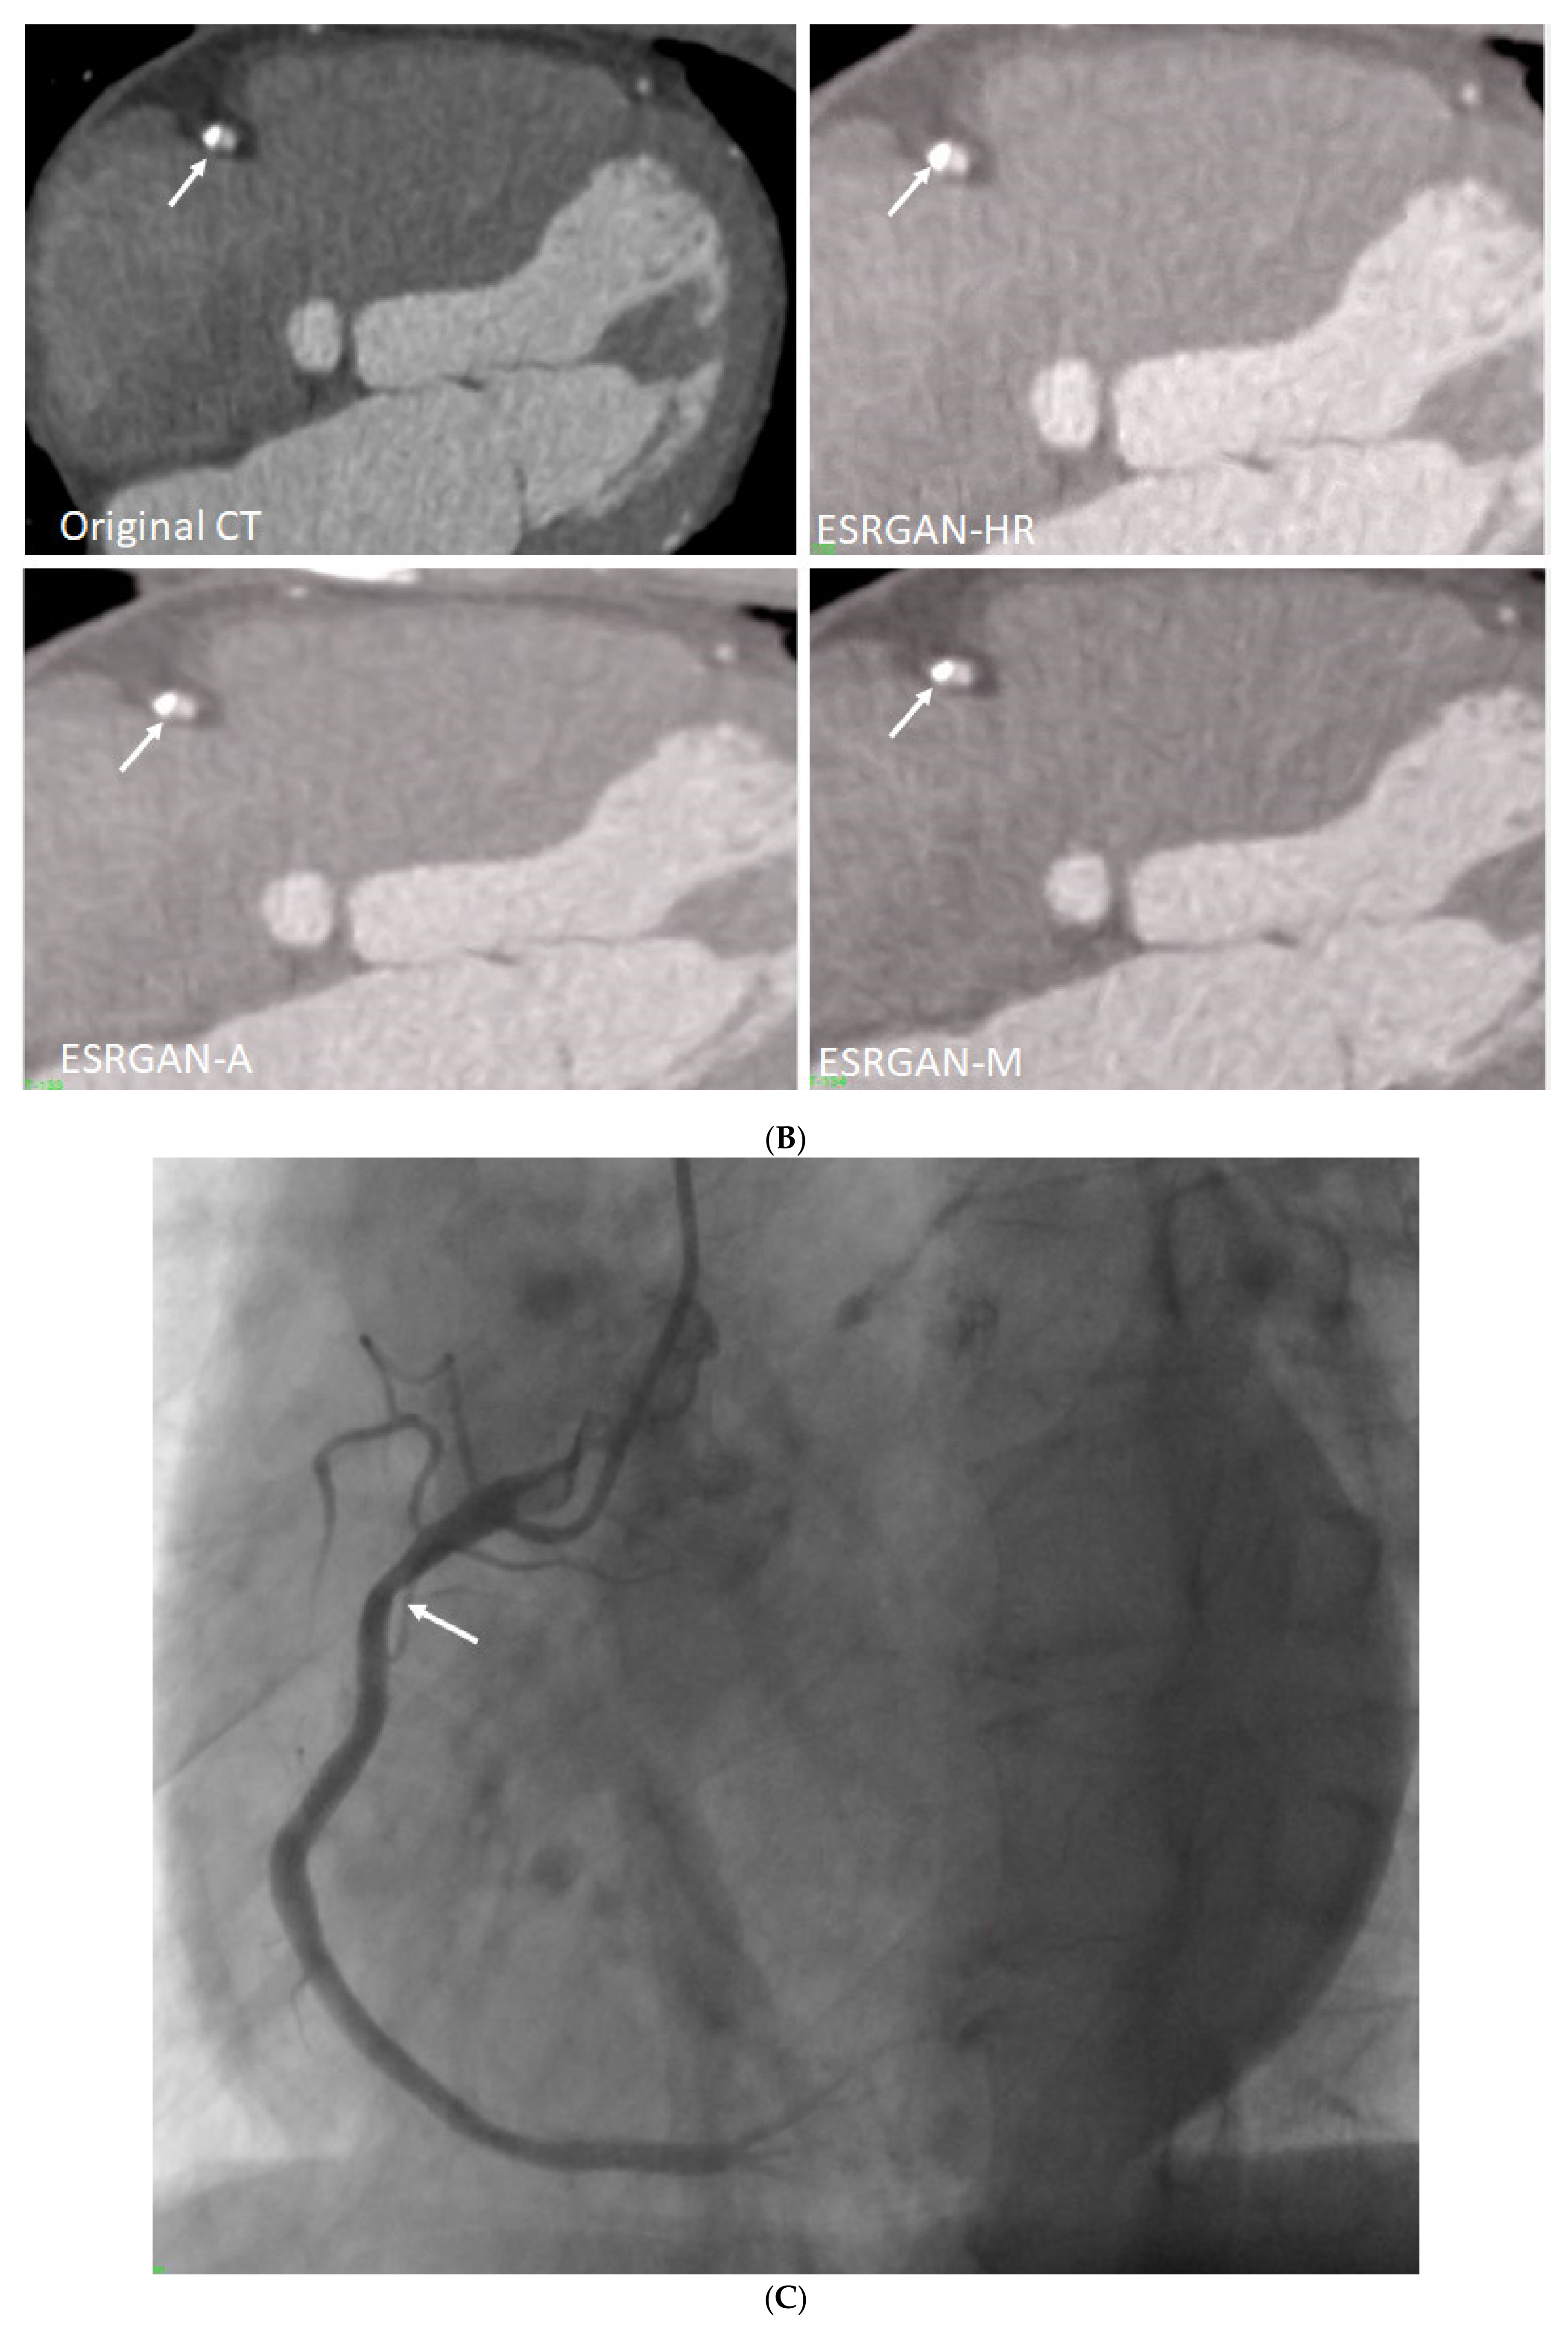

1. Introduction

2.2. Deblooming in CCTA

2.5. Reduction of Blooming Artifact by ESRGAN